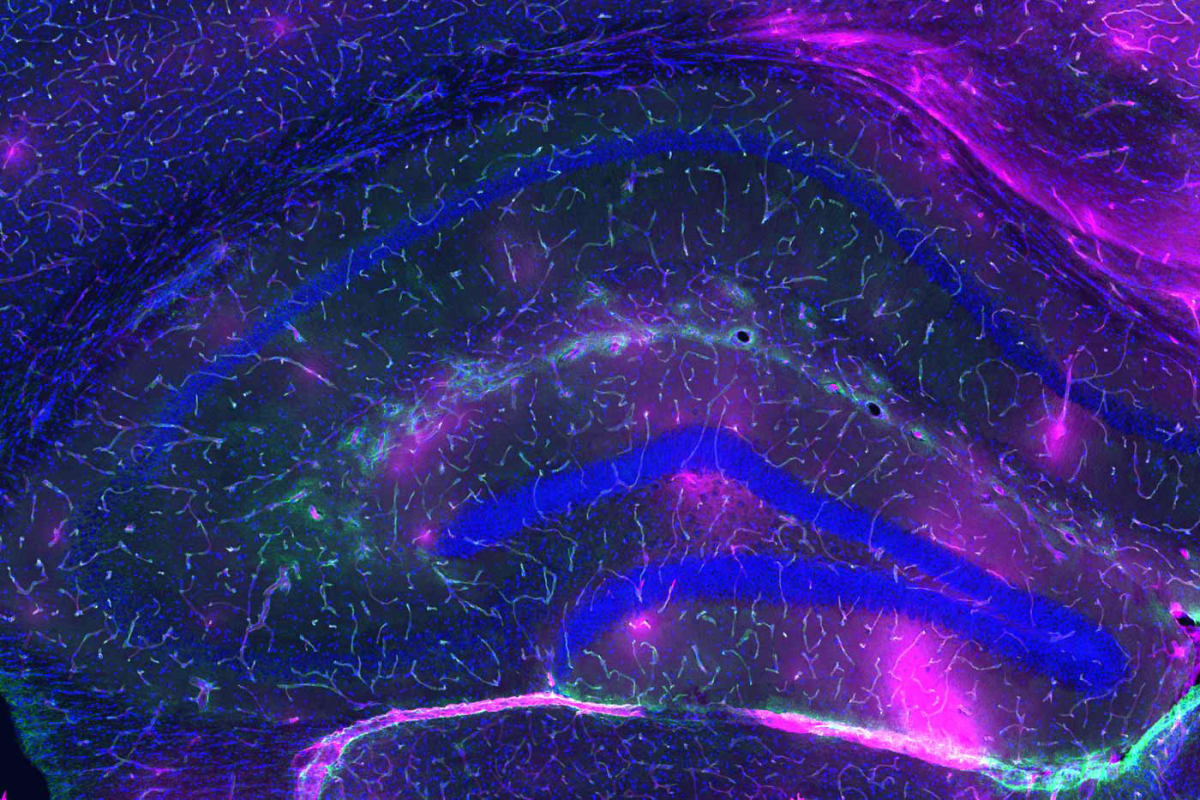

Para comprender la magnitud de este descubrimiento, debemos asomarnos a la microanatomía de la frontera cerebral. La BHE es una interfaz vascular altamente selectiva que separa el cerebro de la circulación sistémica, formada por un mosaico celular inexpugnable: células endoteliales microvasculares cerebrales (BMEC), astrocitos y pericitos.

A diferencia de otros vasos sanguíneos, las BMEC carecen de poros o fenestraciones. Están selladas por uniones estrechas (compuestas por proteínas como claudinas y ocludinas), que restringen severamente el paso de sustancias, permitiendo solo la entrada de nutrientes esenciales y orquestando la expulsión meticulosa de neurotoxinas como el amiloide-beta.

Para medir la magnitud de esta degradación en el laboratorio, los científicos no observan murallas de piedra, sino el flujo de marcadores microscópicos. Evalúan la velocidad exacta a la que fluidos y moléculas, como si fueran invasores cruzando un foso, logran traspasar el endotelio celular. Lo que en la juventud era un sello biológico hermético y casi inexpugnable, con la senescencia se convierte en un tamiz permisivo. A través de estas brechas estructurales, las células inmunitarias periféricas y las citoquinas inflamatorias logran penetrar en el cerebro.

Esta infiltración desata una tormenta de neuroinflamación crónica que hiperactiva la microglía y altera el delicado ecosistema en el que habitan las neuronas, aquellas a las que Cajal bautizó poéticamente como “las misteriosas mariposas del alma”. Este asedio inflamatorio acelera la acumulación de proteínas patológicas, precipitando la ruina cognitiva característica de enfermedades como el Alzheimer y el Parkinson.

Imagen de portada